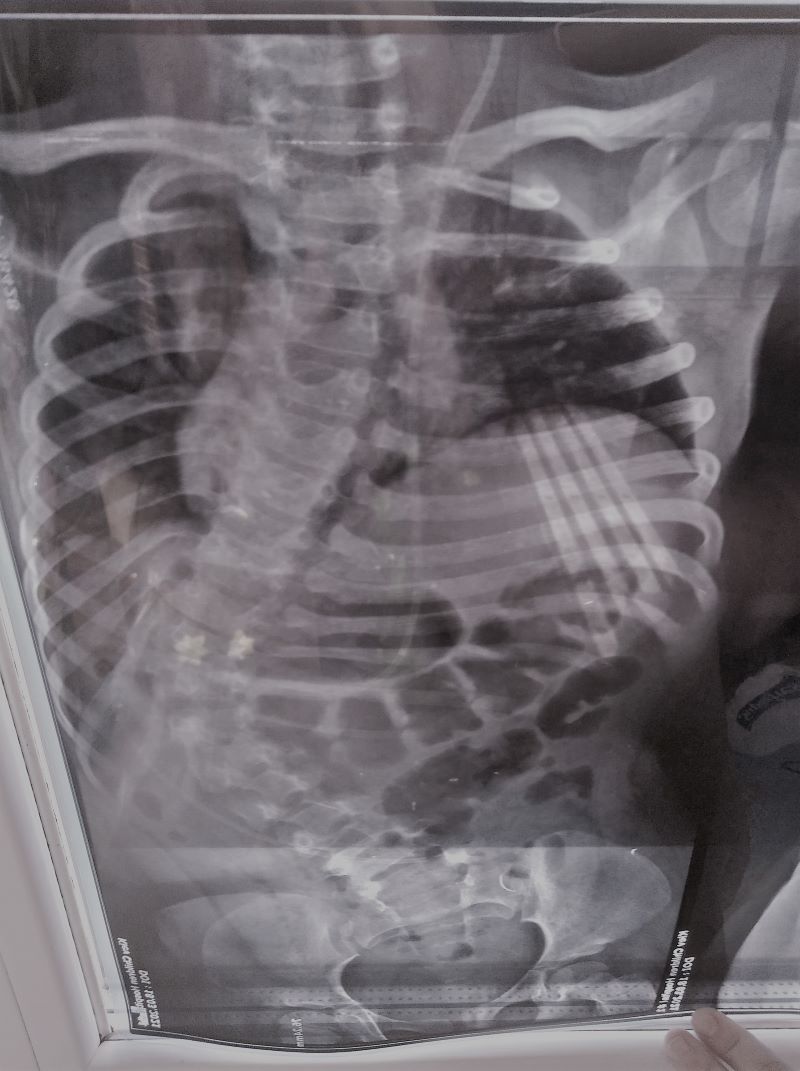

Лещинська Ліза, 5 рочків, спина-біфіда, сколіоз

300 тис.грн. Це дуже великий , але вкрай важливий збір для життя однієї маленької дівчинки. Ліза – довгоочікувана і бажана донечка, народилася с важкою вродженою вадою – розщеплення хребта. Першу операцію перенесла вже на другий день після народження. Потім – ще кілька втручань. Родина постійно займається з дитиною: курси реабілітацій, лфк, заняття вдома. Лізонька зростає дуже доброю, веселою та розумною. Але, не зважаючи на всі заняття, в дитини прогресує життєзагрожуючий сколіоз. Через викривлення хребта, стискаються и не можуть нормально зростати та функціонувати внутрішні органи: серце, легені, печінка…

Світовий досвід в таких випадках – це встановлення системи імплантатів, які вирівнюють хребет дитини. Ця система встановлюється на багато років, але кожний певний період часу мультидисциплінарна команда хірургів-ортопедів та нейрохірургів Охматдиту будуть робити ревізії для переналаштування системи відповідно до росту дитини. Лізоньку і родину чекає дуже довге і важке випробування. І їм потрібна наша допомога, бо таких коштів на закупівлю системи імплантатів у родини немає.